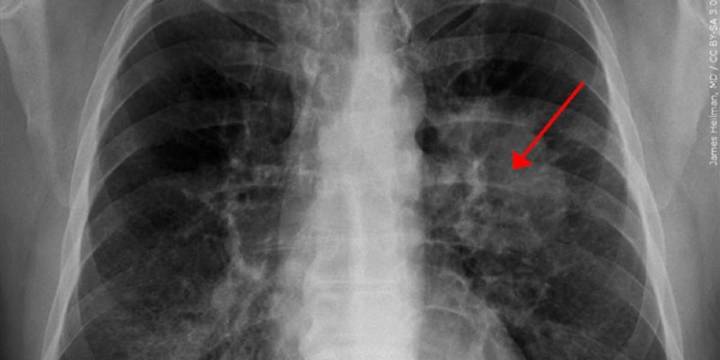

BATON ROUGE, La. (WAFB) - Lung Cancer Awareness Month is observed in November. Whether it’s the risk factors, prevention, screening, or symptoms, understanding these items is critical.

The American Cancer Society says lung cancer is the second most common cancer and the leading cause of cancer death in the United States.